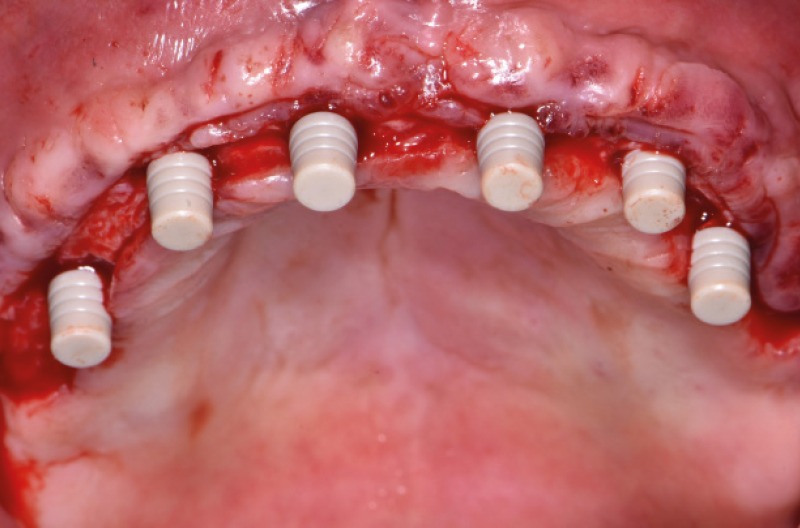

Ho riaperto il mascellare superiore con un lembo a spessore parziale palatino e con scarichi solo distali per limitare al minimo il trauma allŌĆÖosso perimplantare; dopodich├® ho scelto i monconi MUA pi├╣ idonei, tutti GH 1,5 mm uno diritto, tre angolati a 15┬░ e due angolati a 25┬░. Una volta parallelizzati, ho attivato i monconi MUA negli impianti e avvitato gli adattori Conic per trasformarli in monconi MUA-Conic. Dopo aver suturato il lembo, ho attivato le cappette Fixed sui monconi MUA-Conic e poi si ├© proceduto alla ribasatura della protesi opportunamente scaricata in corrispondenza dei monconi MUA-Conic. Durante la procedura intraorale di inglobamento delle cappette Fixed, la protesi si ├© autocentrata in occlusione con la protesi conometrica fissa provvisoria inferiore. Infine la protesi ├© stata rifinita, riposizionata in bocca e attivata (Figg. 30-37). A distanza di un mese entrambe le Toronto provvisorie sono state rimosse e ribasate per un migliore condizionamento del tessuto gengivale (Fig. 38).

Fig. 30 – Riapertura del superiore con lembo a spessore parziale

Fig. 31 – Monconi di prova inseriti negli impianti

Fig. 32 – Posizionamento e parallelizzazione dei monconi MUA

Fig. 33 – Adattatori Conic avvitati sui MUA per trasformazione in monconi MUA-Conic

Fig. 34 – Vista occlusale dei monconi MUA-Conic

Fig. 35 – Cappette Fixed posizionate sui monconi MUA-Conic